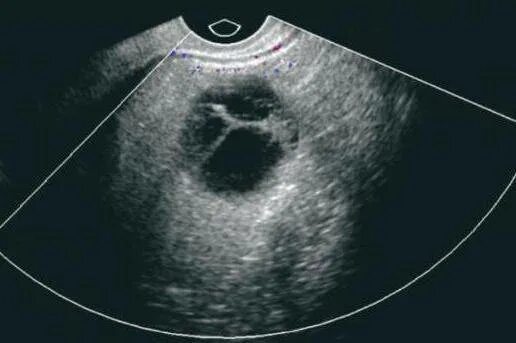

Тянущая боль в яичнике